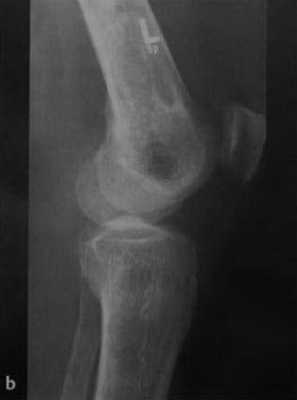

а, b Инфаркт зрелого костного мозга. (а) Сагиттальная протонная плотно-взвешенная МРТ с подавлением МР-сигнала от жировой ткани. Изображение демонстрирует гирляндовидный склеротический край и центральный участок с сигналом жирового костного мозга. Множественные некротические зоны расположены преимущественно в метадиафизальной области, однако несколько находятся непосредственно рядом с суставом, в связи с чем имеется риск уплощения суставных поверхностей;

b) Рентгенологическое исследование демонстрирует выраженный склеротический край и центральный участок снижения рентгенопрозрачности в дистальном отделе бедренной кости и в большеберцовой кости. Проксимальный отдел бедренной кости демонстрирует участок частичного грубого склероза, который иногда трудно отличить от энхондромы.